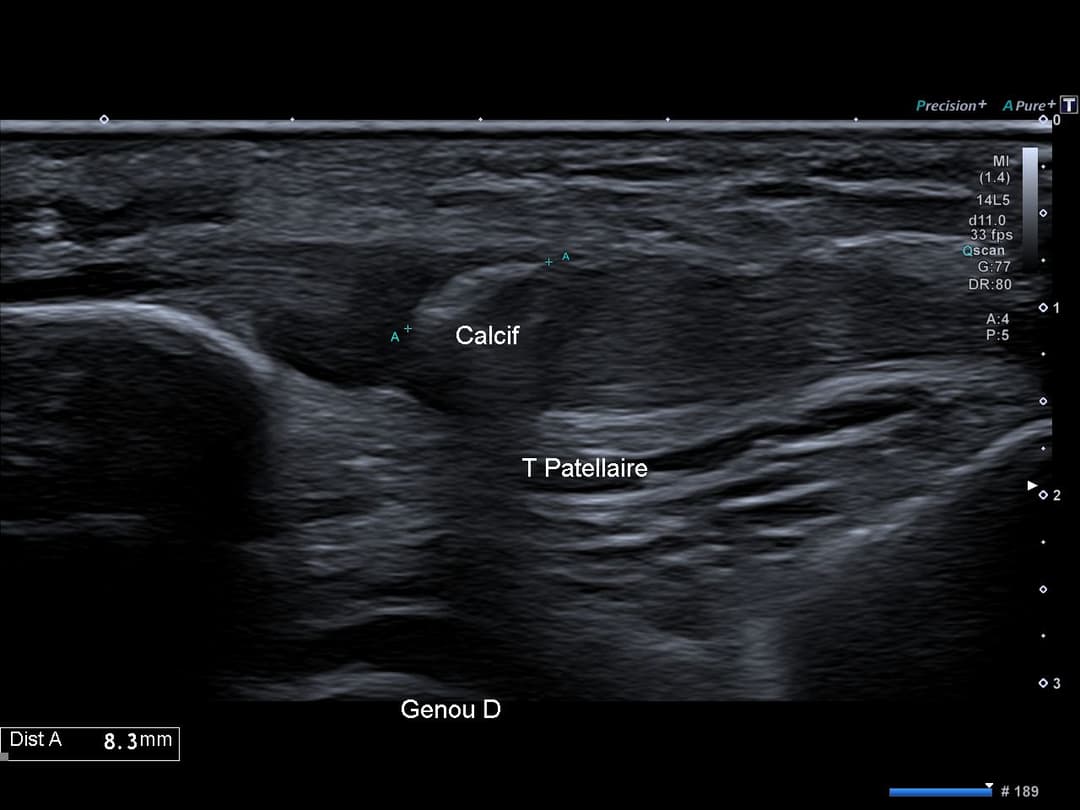

Calcification intra tendineuse corporéale ovoïde non atténuante de 8 mm.